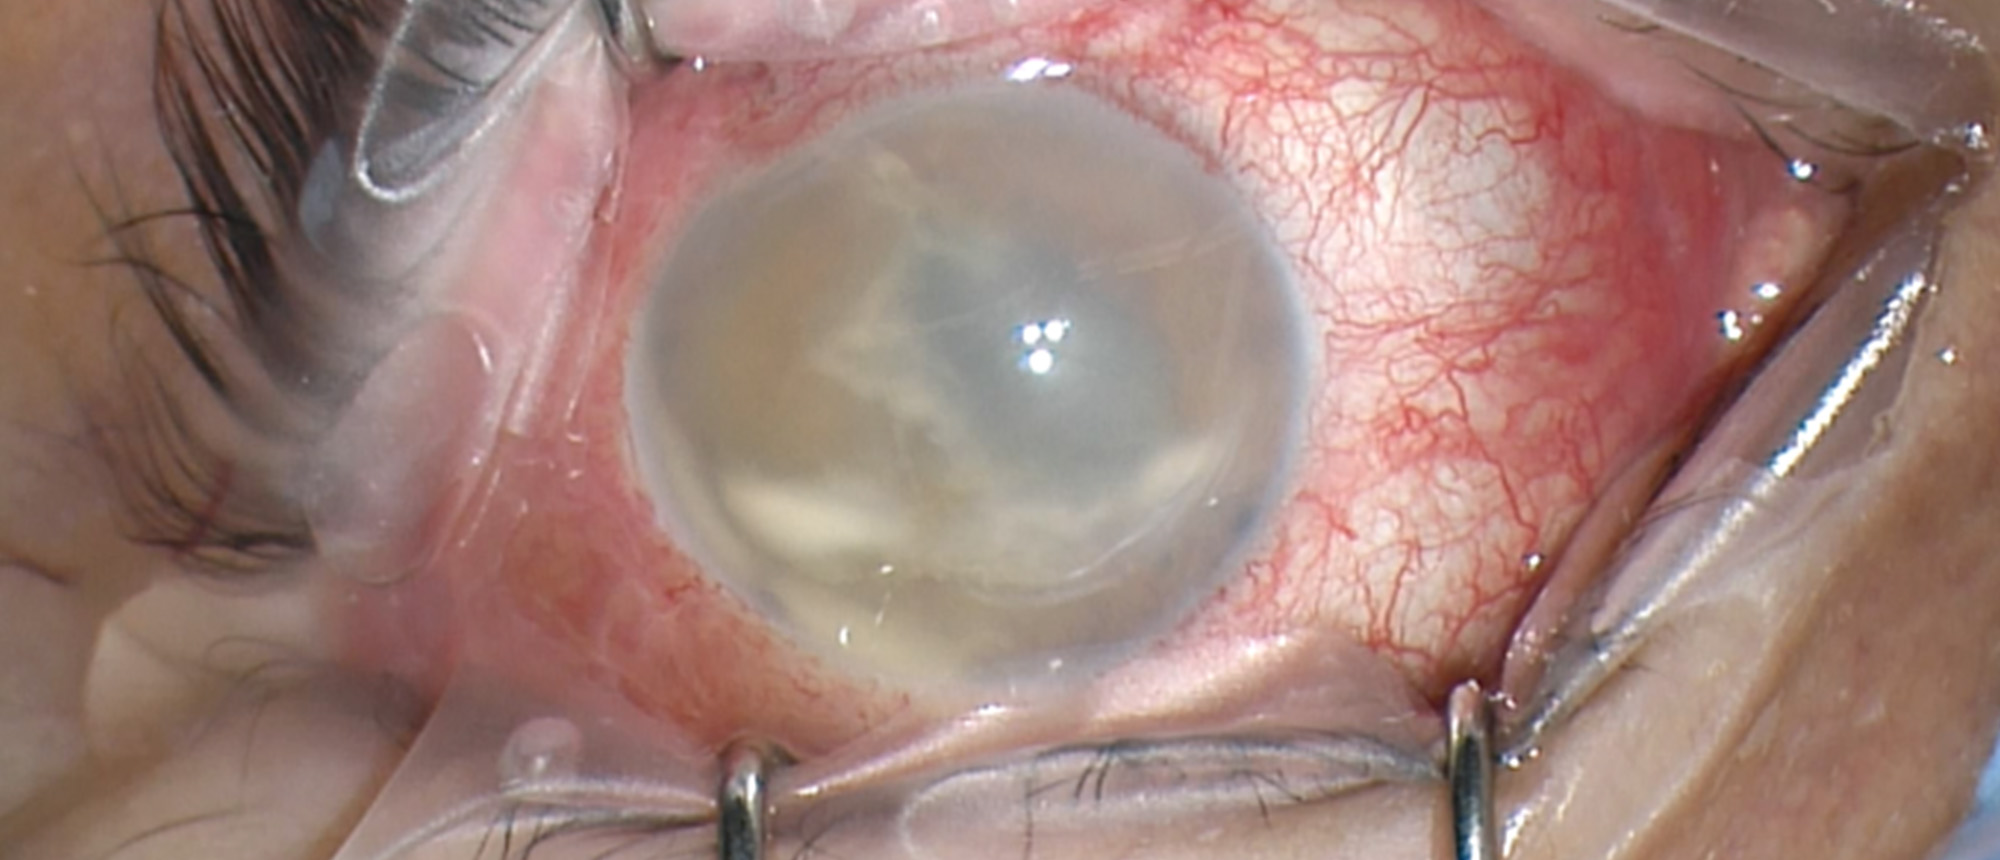

Diabetes Managed with Anterior Chamber Islet Cell Transplant A patient with past medical history of uncontrolled diabetes and open globe injury of the right eye presents with blurred vision in her left eye. She had LP vision in her right eye. Her examination demonstrated changes consistent with pri…